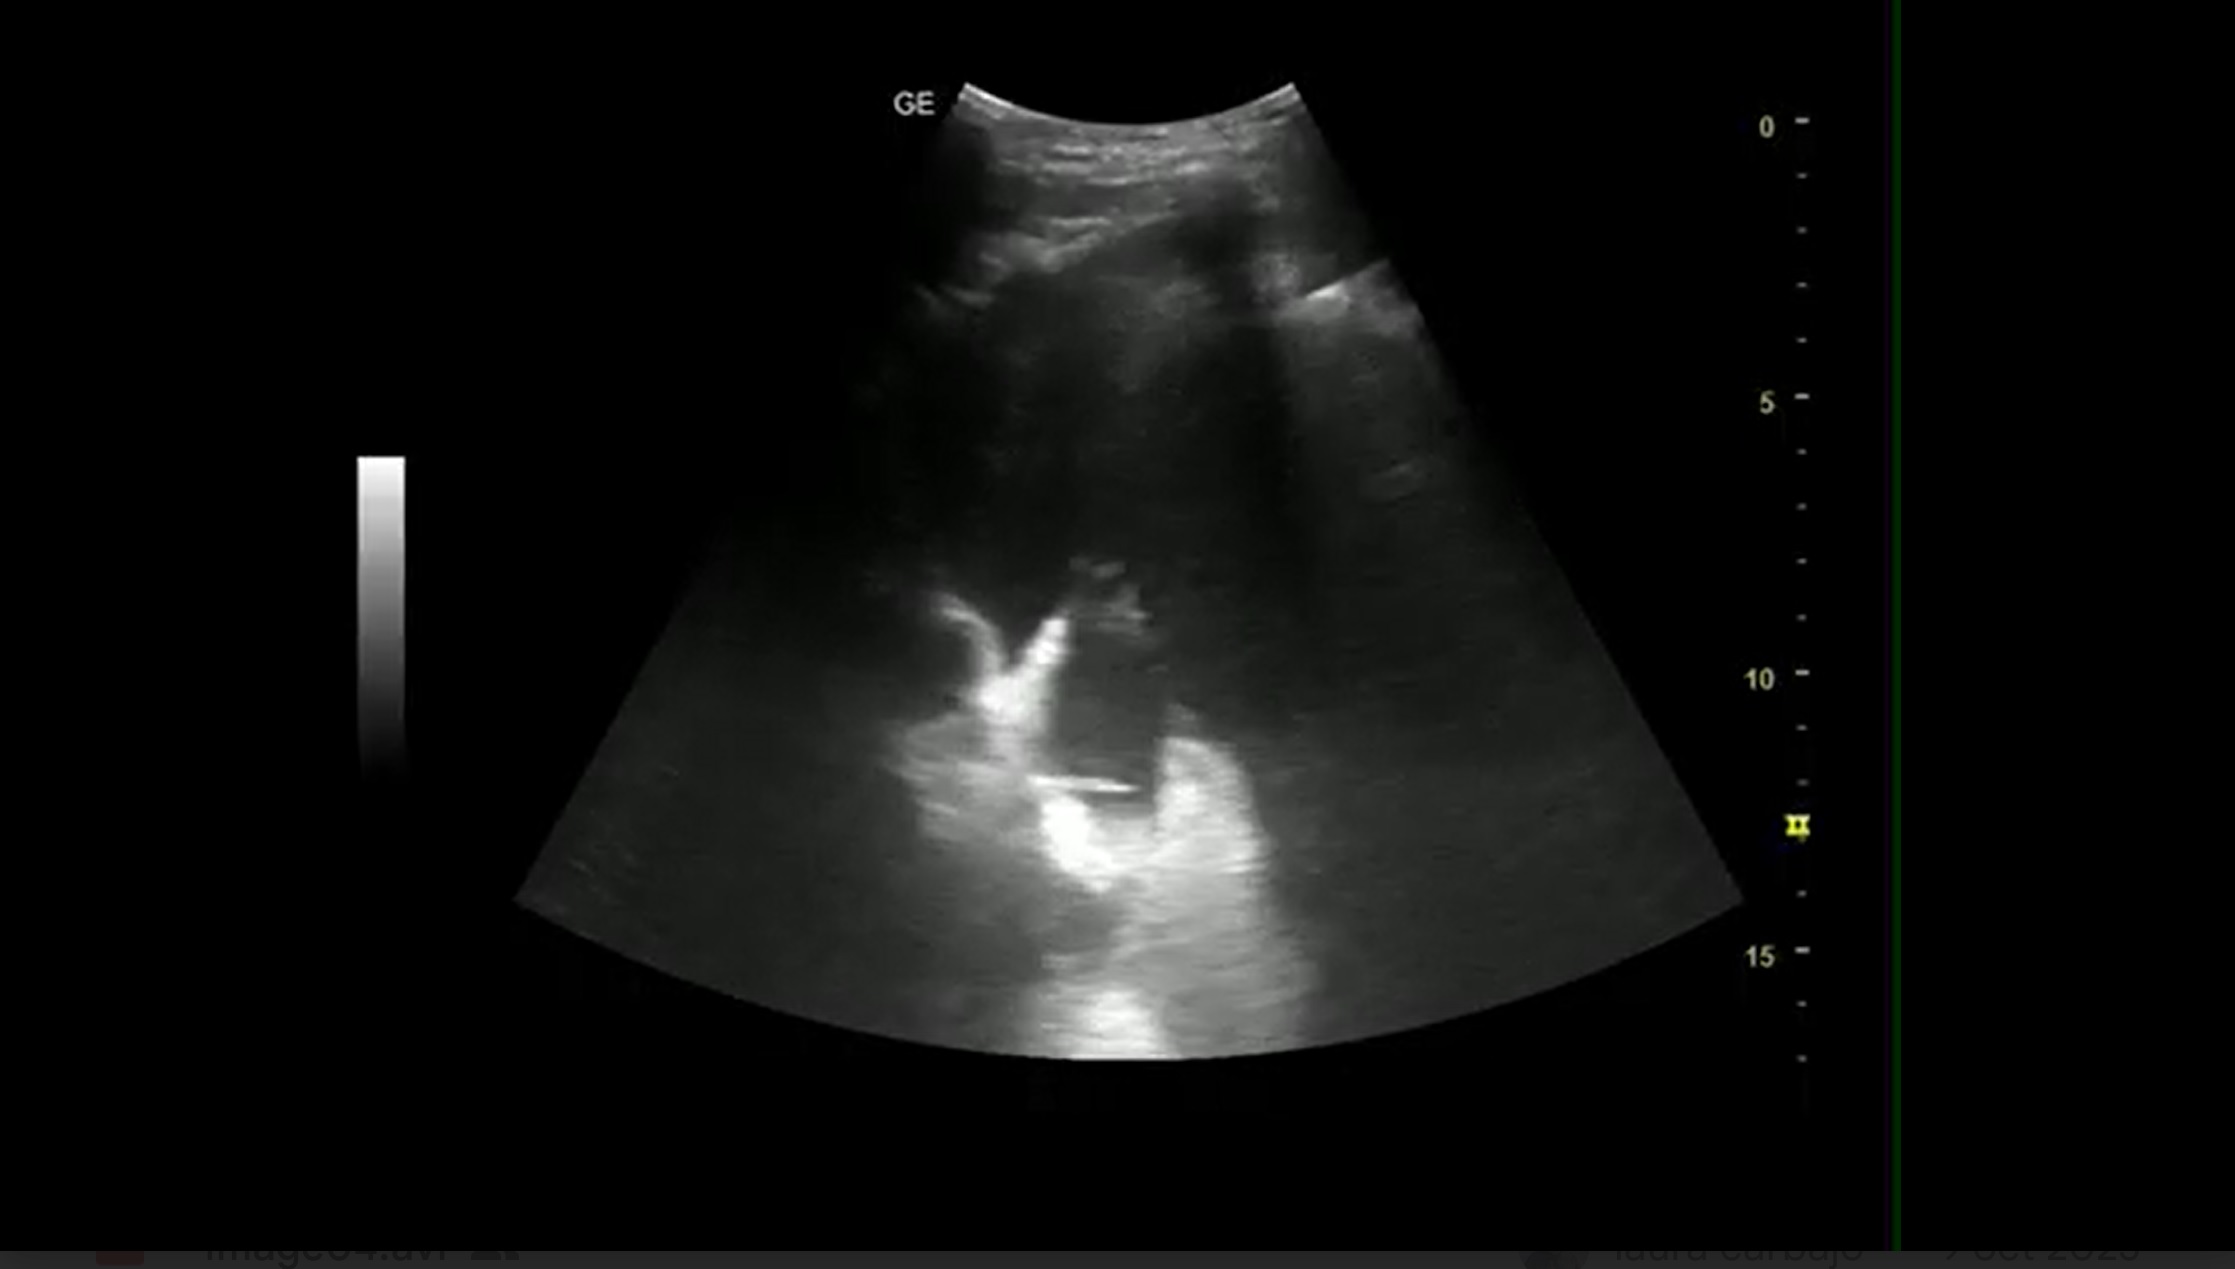

Las imágenes más relevantes observadas revelan los siguientes signos ecográficos:

1. Signo de la medusa: refleja el movimiento ondulante que presenta el pulmón consolidado por el derrame.

2. Hepatización pulmonar: la densidad ecográfica del pulmon se hace similar a la del hígado.